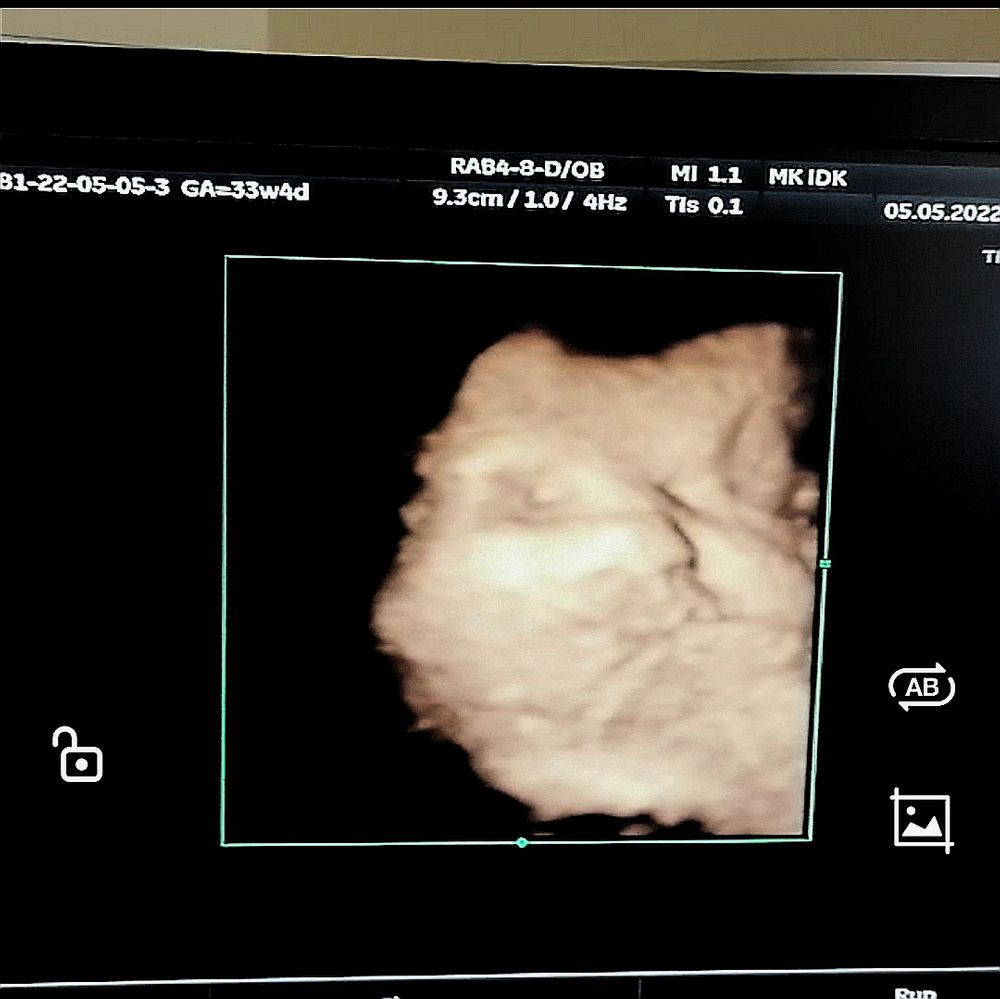

3д узи 🥰

Тут нам по дате переноса 34 недели и 1 день, по размерам - 35 недель и 2 дня)

Девочки, насколько у вас детки родились похожими с фотографиями с 3д узи? 😄